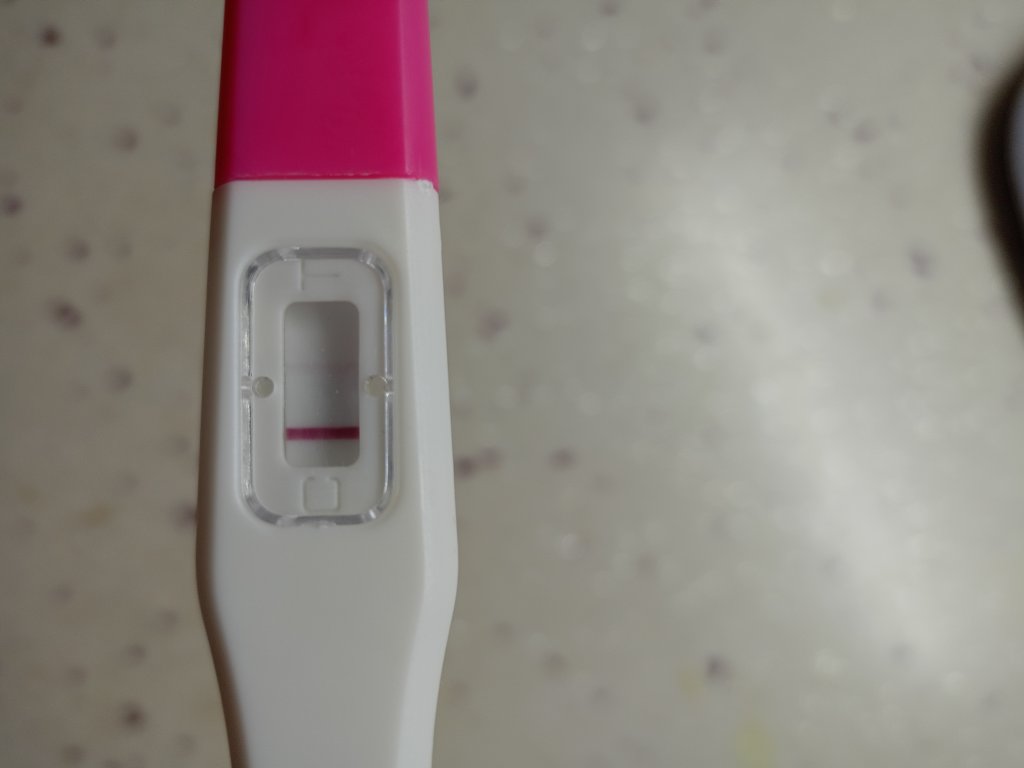

Merhaba kızlar ben reglme 2 gün kala erken gebelik testi yaptım silik çizgi çıktı snra emin olmak için bir tane daha yaptım oda silik cıktı bu gun regl gunum olmadım gittim normal gecelik testi yaptım onda da çok silik çizgi cıktı sizdn fikir almak istiyorum sizce var mı testleri buraya koycam karartma yaptım

Erken gebelik testi